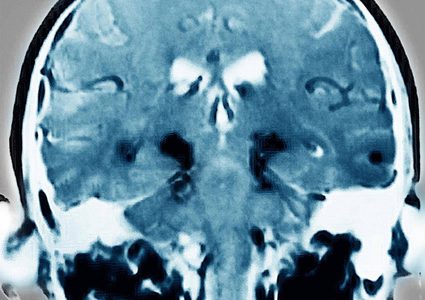

أعلن باحثون أميركيون أن مريضا بالشلل الرعاش (باركنسون) يبلغ من العمر 69 عاما، تمكن من ربط حذائه وممارسة السباحة وركوب الدراجة مجددا، بعد زرع خلايا جلدية …

أفادت دراسة حديثة توصل عدد من العلماء إلى أهمية العمل على تحفيز بطاريات خلايا الدماغ التي تسمى «الميتوكوندريا» باستخدام النبضات الكهربائية من أجل علاج مرض الباركنسون، …